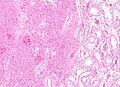

| LM | cytoplasmic vacuolization, cytoplasm -- clear to eosinophilic, +/-Reinke crystals (cylindrical crystalloid -- eosinophilic cytoplasmic bodies), +/-nucleoli common, round nuclei |

- Vacuolization (cytoplasm) - key feature.

- Cytoplasm - clear to eosinophilic - important.

- Usually eosinophilic.

- Reinke crystals - classic finding, usually not present.

- Cylindrical crystalloid eosinophilic cytoplasmic bodies.

- Nucleoli common.

- Round nuclei.

Mass of Right Testicle, Radical Orchiectomy: - Leydig cell tumour. Comment: The tumour consists of polygonal cells with abundant eosinophilic cytoplasm, round nuclei with prominent nucleoli. Features suggestive of malignancy are absent. The tumour stains with calretinin, Melan A and inhibin. It is negative for AE1/AE3, and OCT4. This supports the diagnosis of Leydig cell tumour.